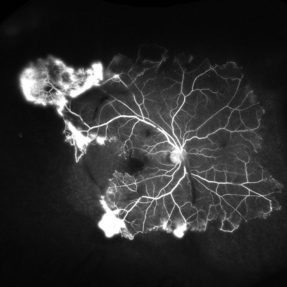

Sickle cell retinopathy (Proliferative) (2 files)

Sickle cell retinopathy (Proliferative) (2 files)

Proliferative sickle retinopathy (1 file)

Proliferative sickle retinopathy (1 file)

Proliferative Sickle Cell Retinopathy (Stage3) (10 files)

Proliferative Sickle Cell Retinopathy (Stage3) (10 files)